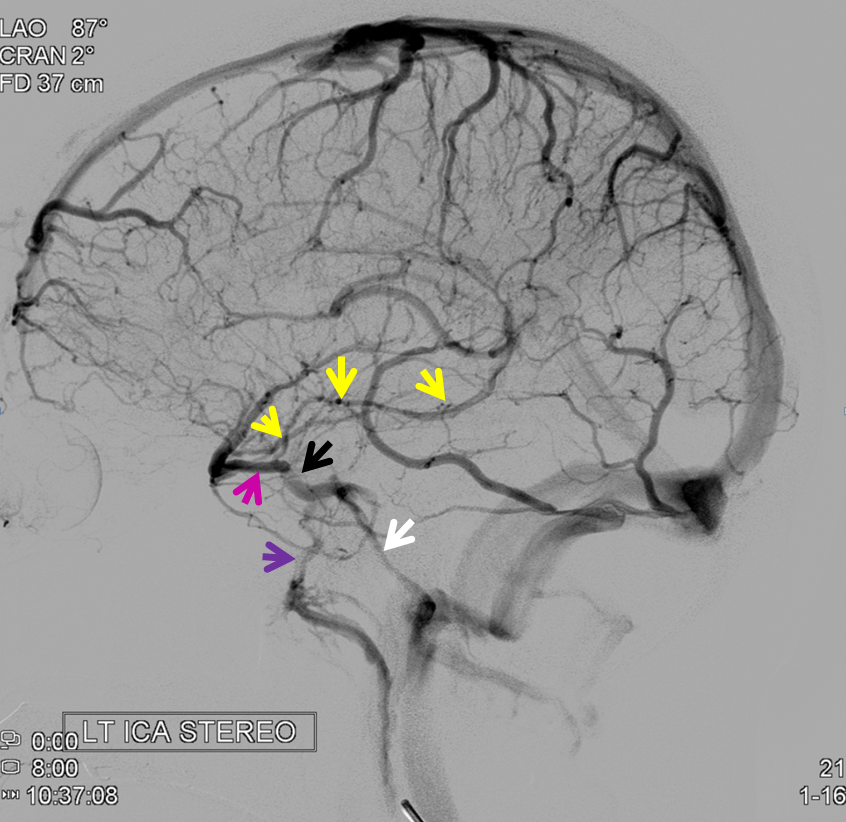

Below is an example of as large an inferior sagittal sinus (white) as one is likely to ever see under non-pathologic circumstances. Why is this sinus so large? Again, the answer is that veins are like rivers — the inferior sagittal sinus happens to be receiving a completely benign, nonpathologic mesial anterior frontal vein (blue arrows). However, the increased inflow into the Galen system has likely resulted in alternate drainage of the basal vein (purple) into the superior petrosal sinus via the lateral mesencephalic vein (black) — see deep venous system and veins of posterior fossa pages for more info. Also notice a large emissary vein (pink)

Stereo of the same